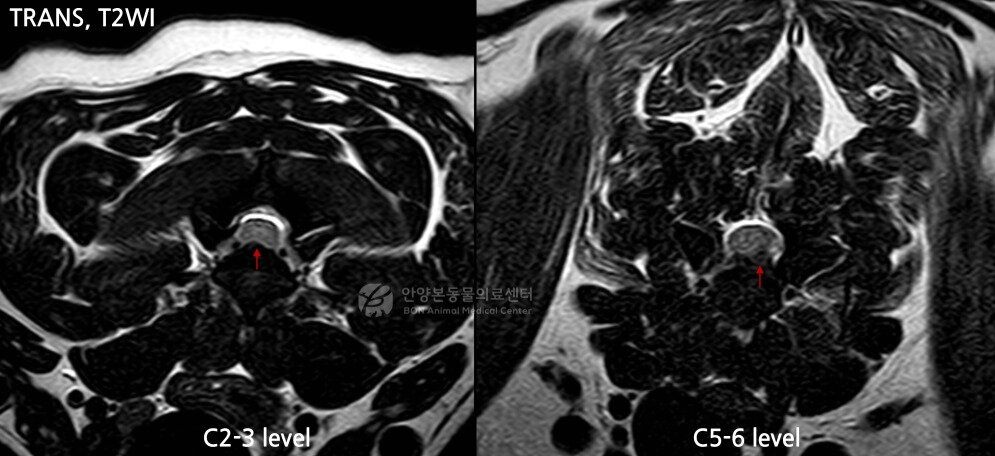

본문 이미지 - 사지마비 증상을 보인 환견의 MRI 영상. 경추 2~3번(C2-3) 부위에서 신경 압박이 확인됐고, 특히 경추 5~6번(C5-6) 부위에서는 디스크가 한쪽으로 심하게 탈출하며 척수를 강하게 누르고 있었(본동물의료센터 제공). ⓒ 뉴스1

사지마비 증상을 보인 환견의 MRI 영상. 경추 2~3번(C2-3) 부위에서 신경 압박이 확인됐고, 특히 경추 5~6번(C5-6) 부위에서는 디스크가 한쪽으로 심하게 탈출하며 척수를 강하게 누르고 있었(본동물의료센터 제공). ⓒ 뉴스1